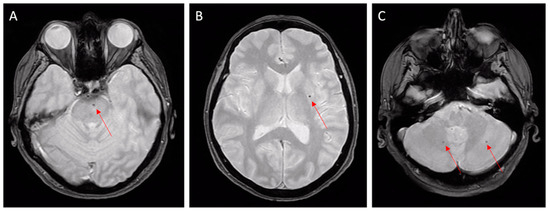

2.3. Diagnosis of CAA

- Charidimou, A.; Boulouis, G.; Frosch, M.P.; Baron, J.C.; Pasi, M.; Albucher, J.F.; Banerjee, G.; Barbato, C.; Bonneville, F.; Brandner, S.; et al. The Boston criteria version 2.0 for cerebral amyloid angiopathy: A multicentre, retrospective, MRI-neuropathology diagnostic accuracy study. Lancet Neurol. 2022, 21, 714–725. [Google Scholar] [CrossRef]